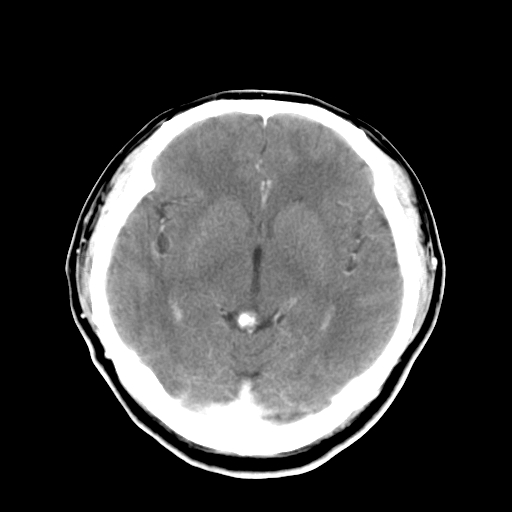

标题: CT16447B:(续)增强扫描图像。

患者今日做ct增强检查,现补传增强扫描图像。

松果体钙癍增大,无其他改变,定不了性

一般认为大于1cm为异常。